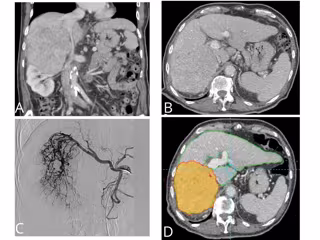

El doctor Arturo del Toro, especialista en radiología intervencionista del Vithas Xanit Internacional, señala que esta técnica, denominada radioembolización, "es un tratamiento multidisciplinar que implica a medicina nuclear y radiología intervencionista, además de los servicios de digestivo, cirugía digestiva y radiofísica".

"La radioembolización es una terapia dirigida que consiste en que millones de microesferas de cristal radioactivas con itrio-90 producen una ablación intravascular en el lecho de la lesión", matiza el doctor.

Además, indica que "estas microesferas del grosor de un cabello humano se dirigen directamente al tumor hepático a través de la arteria hepática, donde se introducen por medio de un catéter".

"Las microesferas fluyen directamente hacia el tumor a través de los vasos sanguíneos del propio cáncer y se alojan permanentemente en el mismo y debido a que el procedimiento incide directamente en el tumor, la radiación destruye las células del cáncer con un impacto mínimo sobre el tejido hepático normal adyacente", afirma.